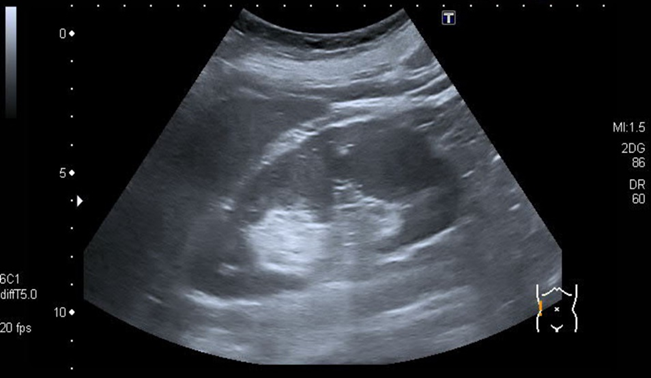

Abdominal ultrasound:

Round, well-circumscribed, highly echogenic renal tumor often located near the renal capsule Ultrasound of the right kidney.

There is a hyperechoic, sharply demarcated, round lesion that is located directly on the renal pelvis without a displacement effect on the organ. This finding is most likely an angiomyolipoma